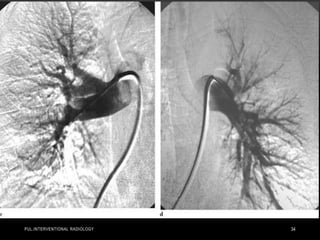

• Pulmonary angiography in a 57-year-old woman in shock from

acute bilateral massive PE. Initial right (a) and left

(b) pulmonary angiograms show near-complete obstruction.

Pulmonary artery pressure was 73/18 mm Hg. Final right (c) and

left

(d) images after suction thrombectomy and catheter-directed

thrombolytic agent injection into each main descending

pulmonary

artery. Pulmonary artery pressure was reduced to 36/16 mm Hg.

(Images courtesy of Daniel Y. Sze.)